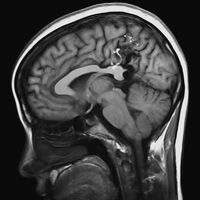

Наночастицы изменят МРТ-диагностику

Инновационные наночастицы для диагностики МРТ разработаны исследователями из Госпиталя МакЛина при Медицинском факультете Гарварда. Так называемые «зеленые» частицы на основе природного белка проникают в головной мозг, быстро проходят через гематоэнцефалический баръер из просвета сосудов в клетки мозга. Частицы обладают способностью транспортировать в нервные клетки определенные химические вещества.

По информации американских ученых, протеин клатрин встречается в клетках живых организмов, в том числе в клетках грибов, растений, простейших организмов, бактерий, животных и конечно, в организме человека. Данный белок выполняет функцию переносчика молекул внутрь клеток. Американские исследователи разработали метод, позволяющий трансформировать клатрин в наночастицы, которые можно использовать в диагностике.

Автор исследования, профессор Виталиано уточняет, что белок клатрин до настоящего времени не подвергался химическим превращениям. Не существует опыта по использованию рекомбинантного клатрина в организме человека. Ученый считает перспективными новые возможности в диагностике, а точнее в медицинской визуализации, которые появились при модификации белка. В головной мозг теперь можно вводить не только контрастные вещества для исследования, но и лекарственные препараты.

Американские исследователи совместили технологию модификации клатрина с присоединением флуоресцентных меток.

В настоящее время ученые изучают возможности применения технологии наночастиц клатрина в МРТ-диагностике. Эффективность МРТ –диагностики с контрастированием повышается почти в 8.000 раз в сравнении с применением контрастного вещества гадопентетата димеглумина, применяемого в современной лучевой диагностике.

Таким образом, появляется возможность уменьшить в 8.000 раз дозу контрастного вещества, вводимого в организм пациентов. Соответственно, практически сводится к нулю риск токсического поражения органов.